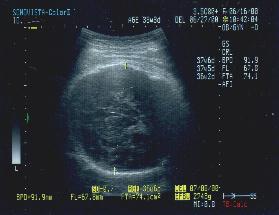

10ヶ月になると写真のように

2600グラム〜3400グラムの間になります

さあ、もうすぐ赤ちゃんに会えますね。